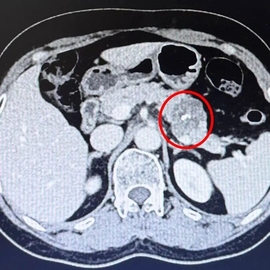

60岁的北湖西路大叔近几天觉得上腹胀痛不适,不想吃东西,大便也未解。